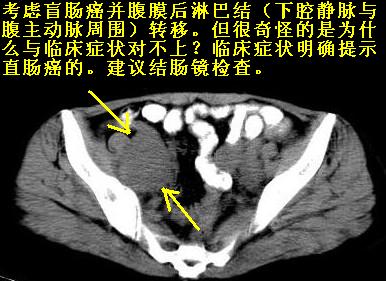

腹膜后多发肿大淋巴结肿大并融合改变;右侧回盲部可见团块样软组织影,不规则;

淋巴瘤?回盲部占位,,淋巴瘤肠道改变?建议进一步检查.

腹膜后诸多淋巴结,右侧髂窝软组织块影,综合患者大便次数、形状改变,考虑结肠回盲部肿瘤

考虑回盲部肿瘤并腹膜后淋巴结转移,建议钡剂灌肠或增强检查。

回盲部可见团块样软组织影,不规则;腹膜后多发肿大淋巴结肿大并融合改变;考虑回盲部肿瘤并腹膜后淋巴结转移,建议钡剂灌肠或增强检查.

双侧盆腔均可见不规则形软组织肿块影,似为结节状影融合而成,但以右侧为甚,腹主动脉与下腔静脉周围亦可见多个肿大淋巴结.

结合临床手术史考虑:盆腔与腹膜后多发性淋巴结转移(原发灶可能是原来的\"子宫肌瘤\"恶变或并非\"子宫肌瘤\";回盲部肿瘤不排除)